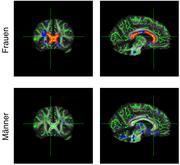

Bei übergewichtigen Frauen traten im Corpus callosum größere Veränderungen (rot markiert) auf als bei den männlichen Testpersonen. Max-Planck-Institut für Kognitions- und Neurowissenschaften